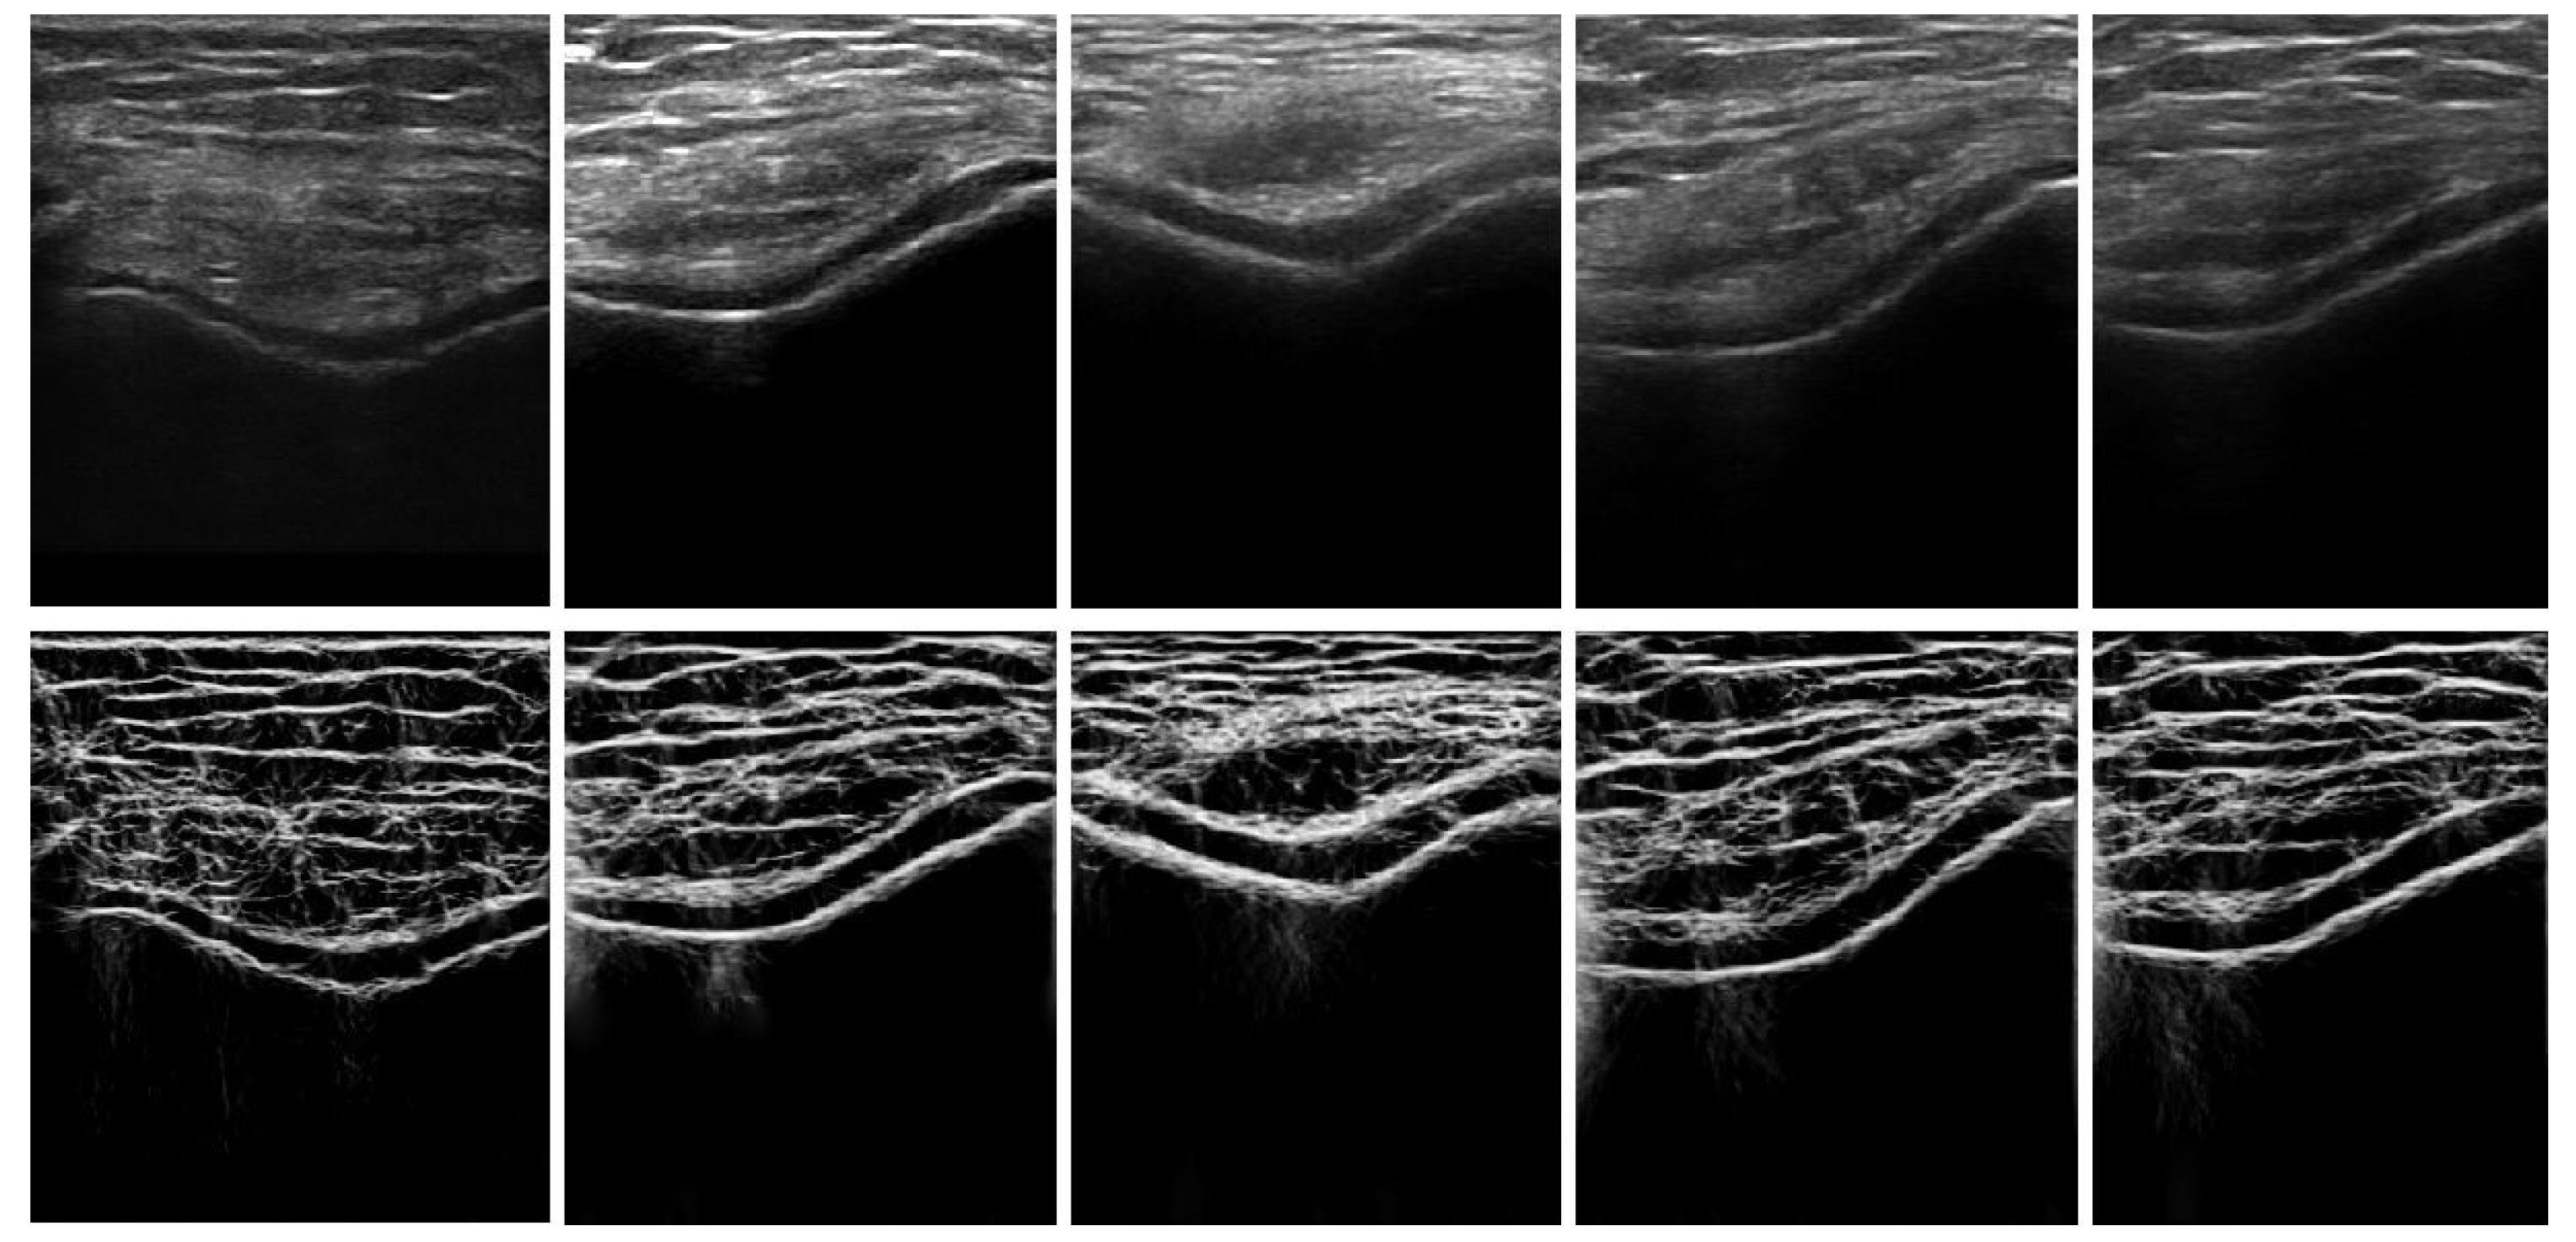

Figure 2.

In vivo ultrasound (US) image enhancement: Top row: In vivo B-mode knee-cartilage US image (). Bottom row: Enhanced knee-cartilage US image ().

In Equation (2), evaluates angular bandwidth as, . denotes the angular separation between neighboring orientations. Figure 2 shows the enhanced image, where the bone–cartilage region is enhanced compared to the original B-mode US image. Investigating the results, we can see that the proposed method provides general enhancement results of the cartilage response profile, independent of image intensity. The enhanced image, , is used as an input to the automated knee-bone surface-localization and cartilage-segmentation method, which is explained in the next sections.